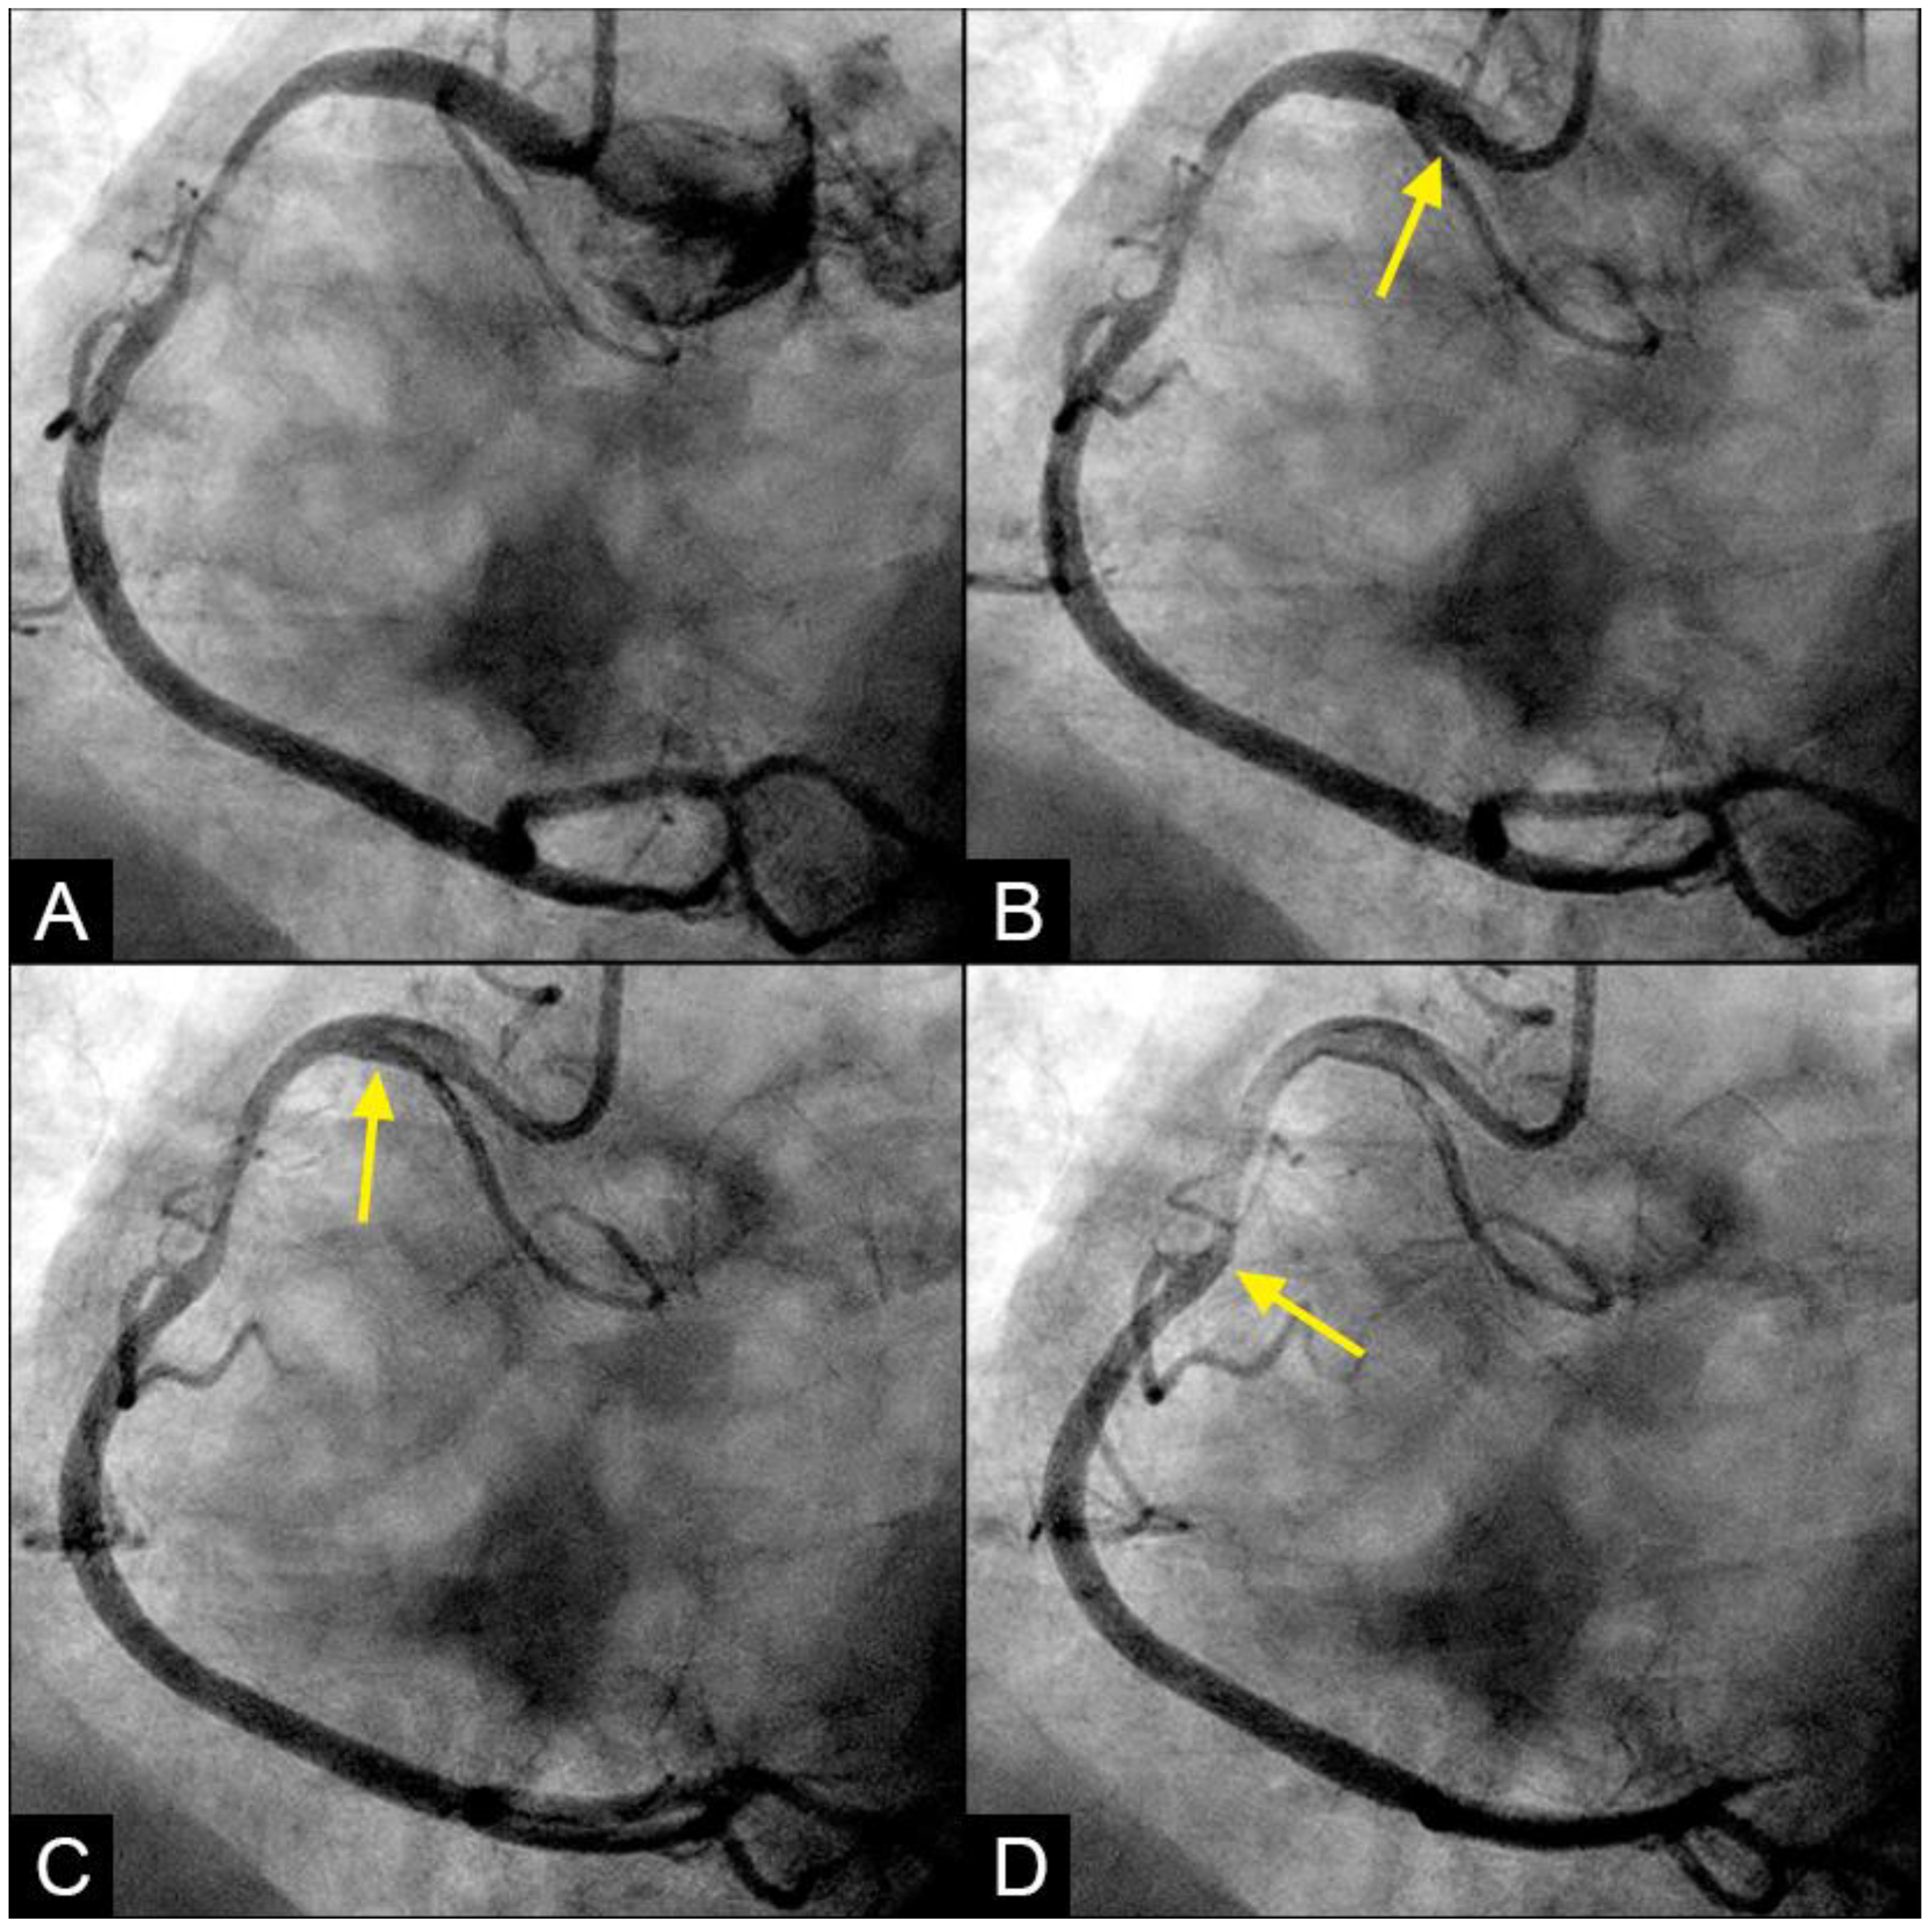

Retrograde flow: In this study, the prevalence and morphological characteristics of the retrograde flow emerged as the most significant and intriguing findings. While retrograde flow is rare in domestic and industrial fluid or air transport systems, it is essential to address and correct it. Conversely, our study revealed that the retrograde flow was relatively common within the iliac arteries and rare in the coronary system. Despite its frequency, the retrograde flow must be prevented due to its potential to cause collisions with degeneration to disorganized flow. The documentation of the retrograde flow in dynamic angiography represents a novel discovery, as it has not been previously reported in the medical literature (Figure 11A,B).

Figure 11.

(A,B) Collision of the retrograde against the antegrade flow with resulting disorganized flow distal to the collision site. (A) In the mid-segment of the right coronary artery, the lesion presents a reversed rat-tail configuration. At the point where the antegrade and retrograde flows converge, the antegrade flow predominates. As a result, plaque formation occurs in the disorganized flow zone created by the weak retrograde flow. The reversed rat-tail configuration indicates that the retrograde force is concentrated at the center, leading to the deposition of debris or plaque growth along its edges, with the force increasing from DISTAL to proximal. (B) In contrast, at the interface between the antegrade and retrograde flows in the left anterior descending artery (LAD), the lesion forms in the disorganized flow zone of the weak antegrade flow, situated in the end of the proximal segment of the LAD, where retrograde flow predominates. The rat-tail configuration suggests that the antegrade force is concentrated at the center, resulting in the deposition of debris or plaque growth along its periphery, with the force increasing from PROXIMAL to distal. One interesting detail in angiographic imaging is that the contrast in the predominating zone is much darker: antegrade zone in (A) and retrograde zone in (B).